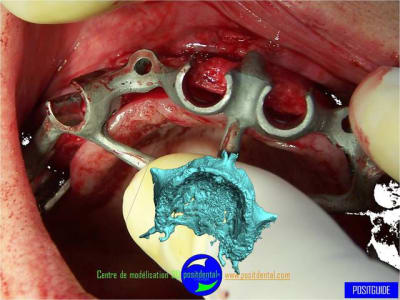

Expansion, condensation guidée

gros travail pour mettre au point un guide pour expansion et belle maitrise chirurgicale !!!

votre avis sur ce cas clinique

précision de la chirurgie guidée condensée

Le guide chirurgical, positionneur d’implants reste en place jusqu’à la pose des implants.